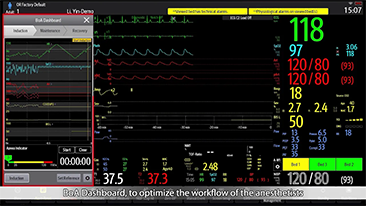

Sinds de oprichting van het bedrijf is Mindray voortdurend op zoek naar nieuwe manieren om het diagnostisch vertrouwen te vergroten. Resona 7 wordt aangestuurd door de meest revolutionaire ZONE Sonography?-technologie. Zijn nieuwe ZST+-tilt de kwaliteit van ultrasoundbeeldvorming naar een hoger niveau door middel van zoneacquisitie en kanaalgegevensverwerking.

Naast de hoogwaardige beeldvormingskwaliteit verbetert de Resona 7 tevens de klinische onderzoeksmogelijkheden met de revolutionaire V Flow voor vasculaire hemodynamische evaluatie, en de intelligentste vlakacquisitie van een 3D-gegevenssets voor de diagnose van het foetale, centrale zenuwstelsel. Met zijn combinatie van de meest intu?tieve, op vingerbewegingen gebaseerde multi-aanrakingsbediening en alle essenti?le klinische functies loopt de Resona 7 voorop in de nieuwe golven van ultrasoundinnovatie.